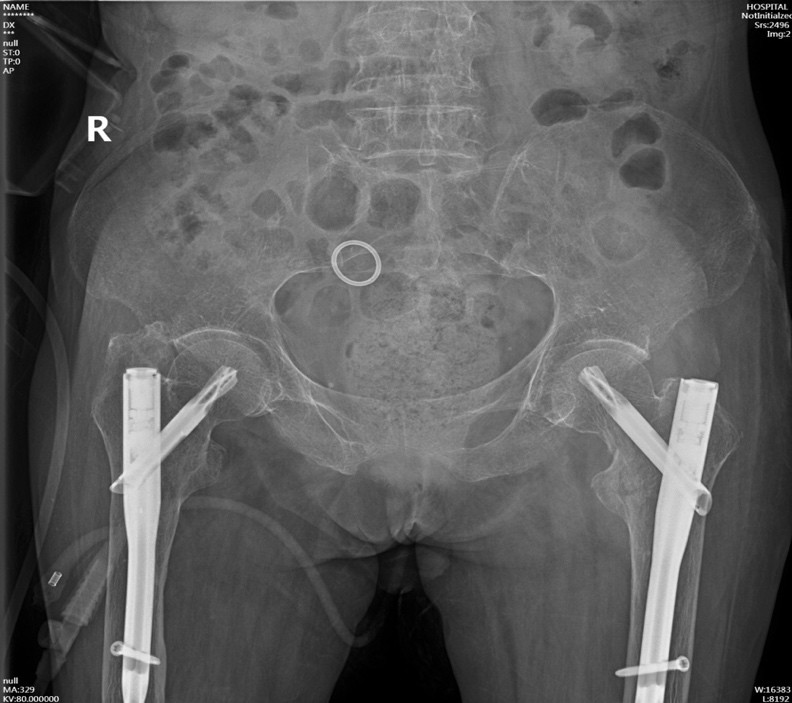

手術(shù)在病人骨折后第三天實(shí)施,手術(shù)當(dāng)天在麻醉科王翔峰主任團(tuán)隊(duì)的緊密協(xié)作,修忠標(biāo)主任醫(yī)師的指導(dǎo)下,鐘水林主治醫(yī)師和韓海醫(yī)師順利地完成了手術(shù),手術(shù)總共耗時30分鐘。

手術(shù)后

從ICU轉(zhuǎn)回我科后,發(fā)揮我院中醫(yī)特色,運(yùn)用中醫(yī)藥對病人進(jìn)行身體調(diào)理。在潘瑋護(hù)士長帶領(lǐng)的護(hù)理團(tuán)隊(duì)精心護(hù)理下,陳奶奶的精神狀態(tài)也一天天好起來。

如今,陳奶奶精神狀態(tài)漸佳,生活能自理,已順利出院,陳奶奶的家屬對此非常感激。